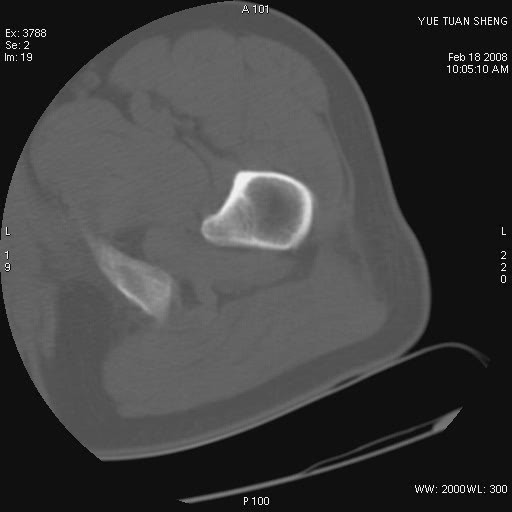

患者,男,56岁,左髋部疼痛1个月,x线:左股骨头高密度影,性质待定,右侧正常。左髋ct如图

左股骨颈区椭圆形磨玻璃样影,边缘明显硬化环环绕,其内见斑点状类钙化高密度影考虑 良性骨病-----骨纤,骨化性纤维瘤,内生软骨瘤。